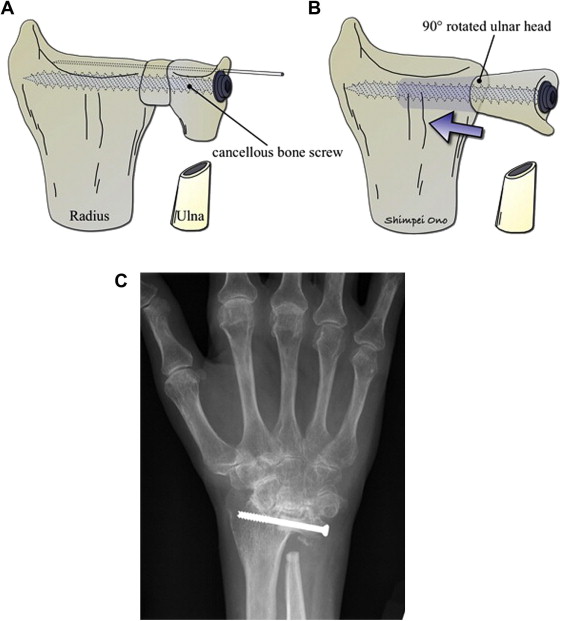

This procedure fuses the ulna head to the sigmoid notch of the radius and creates a pseudarthrosis by a proximal ulnar osteotomy to allow for rotation of the forearm ( Fig. 4 A). This procedure is more appropriate for younger or high-demand patients or those who have ulnar translocation of their carpus. A new joint is created farther down the ulna, stabilizing and preventing abnormal movement of the carpus at the DRUJ, while simultaneously unloading the ulna. This technique allows the ulna to be shortened, thereby transmitting more force across the radius rather than the damaged TFCC. Unfortunately, whether this method can prevent further dislocation of the carpus is still unclear, because robust studies on the long-term outcomes of the Sauve-Kapandji procedure are lacking. A potential problem is the unpredictable fusion of the DRUJ when the bone stock in RA is insufficient. Fujita and colleagues reported on the Modified Sauve-Kapandji procedure (see Fig. 4 B, C), which is designed to solve this problem. The modified procedure involves resecting the distal ulna and making a drill hole in the ulnar cortex of the distal part of the radius. The resected distal ulna is rotated 90°, inserted into the hole made in the distal radius, and secured with cancellous bone screw. The investigators concluded that the technique provides sufficient osseous support of the carpus in patients with poor bone quality.